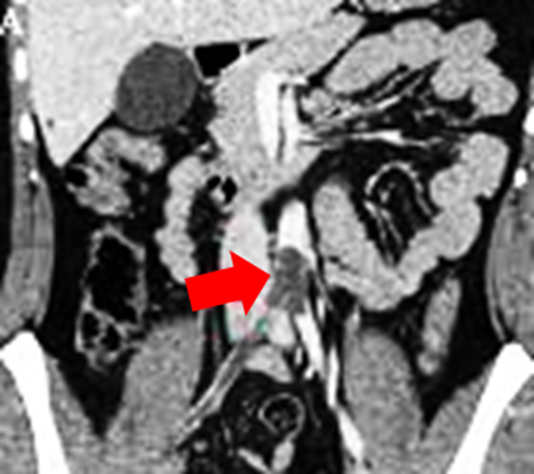

• CT Angiography (CTA):

• Abrupt occlusion of the abdominal aorta at or near the bifurcation

• Lack of contrast enhancement distal to the occlusion

• May show "saddle embolus" at the aortoiliac junction

• Absence of atherosclerosis may suggest embolic etiology